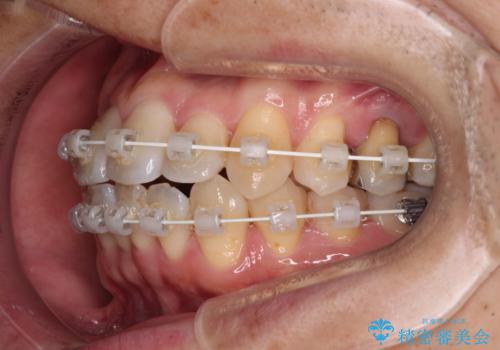

- 審美装置

- 治療期間

- 2年2ヶ月

- 治療回数

- 10-30回